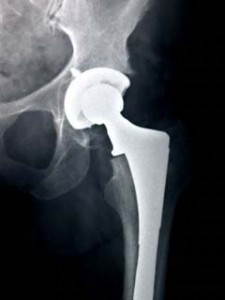

DePuy Complaint - Alhmjell - Join Class Action Lawsuits

DePuy’s ASR Hip System has a critical difference: it uses a metal acetabular cup. By using a By using a metal acetabular cup and a metal femoral ball, the ASR Hip forces metal to rub against metal with ... Fetch Content